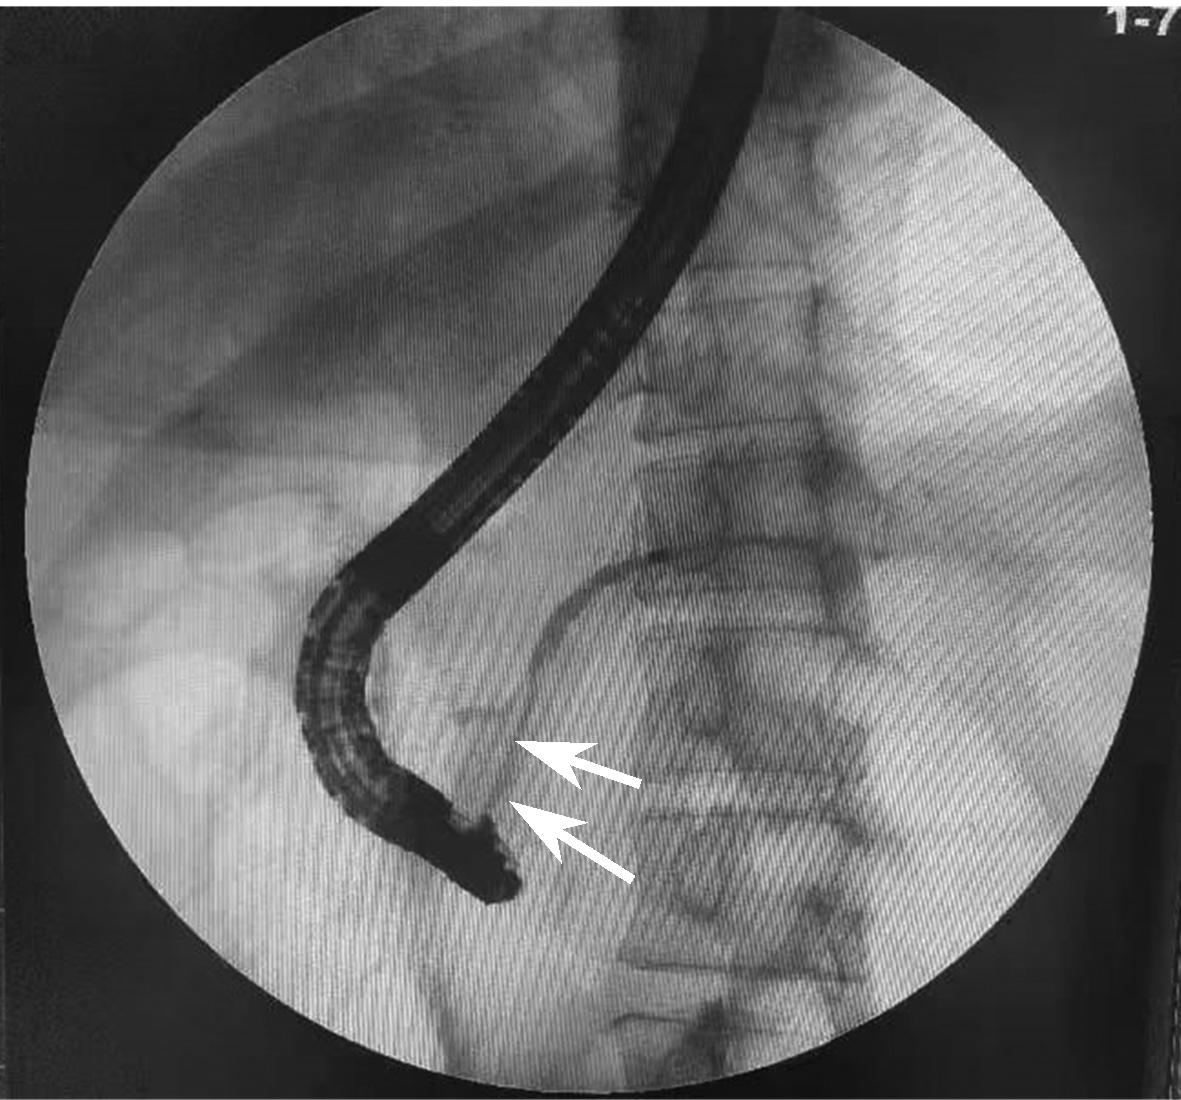

Selection of treatment regimens for pancreatic duct stones: A comparative analysis

Jinbin DONG, Weibing FANG, Yihai SHI

2022, 38(11): 2558-2564. DOI: 10.3969/j.issn.1001-5256.2022.11.023

Abstract(839) HTML (936) PDF (2050KB)(88)

Abstract:

Objective  To investigate the clinical efficacy of endoscopic retrograde cholangiopancreatography (ERCP), laparoscopy, and laparotomy in the treatment of pancreatic duct stones (PDS) by collecting related clinical data, to summarize the experience in selecting treatment regimens for PDS, and to further explore feasible treatment regimens that could maximize and optimize the benefits of PDS patients.  Methods  A retrospective analysis was performed for the clinical data of 131 PDS patients who were treated in Gongli Hospital Affiliated to Naval Medical University from June 2014 to December 2018, and according to the surgical procedure, they were divided into ERCP group with 69 patients, laparoscopy group with 32 patients, and laparotomy group with 30 patients. Related indices were monitored before and after treatment, and surgical outcome was compared between the laparoscopy group and the laparotomy group. The independent samples t-test was used for comparison of normally distributed continuous data between two groups; a one-way analysis of variance was used for comparison between multiple groups, and the least significant difference t-test or the SNK-q test was used for further comparison between two groups. The Mann-Whitney U test was used for comparison of continuous data with skewed distribution between two groups, and the Kruskal-Wallis H test was used for comparison between multiple groups. An repeated measures analysis of variance and the Friedman test were used for comparison of related indices before and after surgery, and the chi-square test was used for comparison of categorical data between groups.  Results  Among the 131 PDS patients, there were 40 patients with type Ⅰ PDS, 76 with type Ⅱ PDS, and 15 with type Ⅲ PDS. There was no significant difference in the distribution of main surgical methods between the laparoscopy group and the laparotomy group (χ2=1.93, P > 0.05). There were significant differences between the laparoscopy group and the laparotomy group in the dynamic changes of white blood cell count, C-reactive protein, procalcitonin, and Homeostasis Model Assessment of Insulin Resistance after surgery (F=24.68, χ2=227.66, F=45.37, F=106.71, all P < 0.05). Compared with the laparotomy group, the laparoscopy group had significantly shorter time of operation, significantly lower intraoperative blood loss, significantly shorter time to first flatus after surgery, a significantly lower frequency of use of pain-relieving drugs, shorter time to extraction of abdominal drainage tube, lower incidence rates of short-term postoperative complications, and a significantly shorter length of postoperative hospital stay (t=-4.80, t=-9.43, Z=-6.78, t=-11.59, Z=-6.77, χ2=9.24, t=-3.60, all P < 0.05). The incidence rate of short-term postoperative complications was 24.64% in the ERCP group, 28.13% in the laparoscopy group, and 66.67% in the laparotomy group, with a significant difference between groups (χ2=17.12, P < 0.05), and the ERCP group and the laparoscopy group had a significantly lower incidence rate of short-term postoperative complications than the laparotomy group (χ2=15.78 and 9.24, P < 0.05 and P=0.02). The treatment response rate was 91.30% in the ERCP group, 93.75% in the laparoscopy group, and 73.33% in the laparotomy group, with a significant difference between the three groups (χ2=7.70, P=0.02), and the ERCP group and the laparoscopy group had a significantly better response rate than the laparotomy group (χ2=5.56 and 4.77, P=0.02 and 0.03).  Conclusion  ERCP is the preferred method for minimally invasive treatment of some patients with type Ⅰ/Ⅱ PDS and is safe and effective with few serious complications. Surgical operation is an important method for the treatment of complex PDS, but with complicated techniques and difficult operation. Compared with laparotomy, laparoscopy has the advantages of small trauma, few serious complications, and high abdominal pain remission rate and can significantly shorten the time of operation, reduce intraoperative blood loss, and shorten the length of postoperative hospital stay. Therefore, laparoscopy should be the preferred regimen for the treatment of complex PDS.